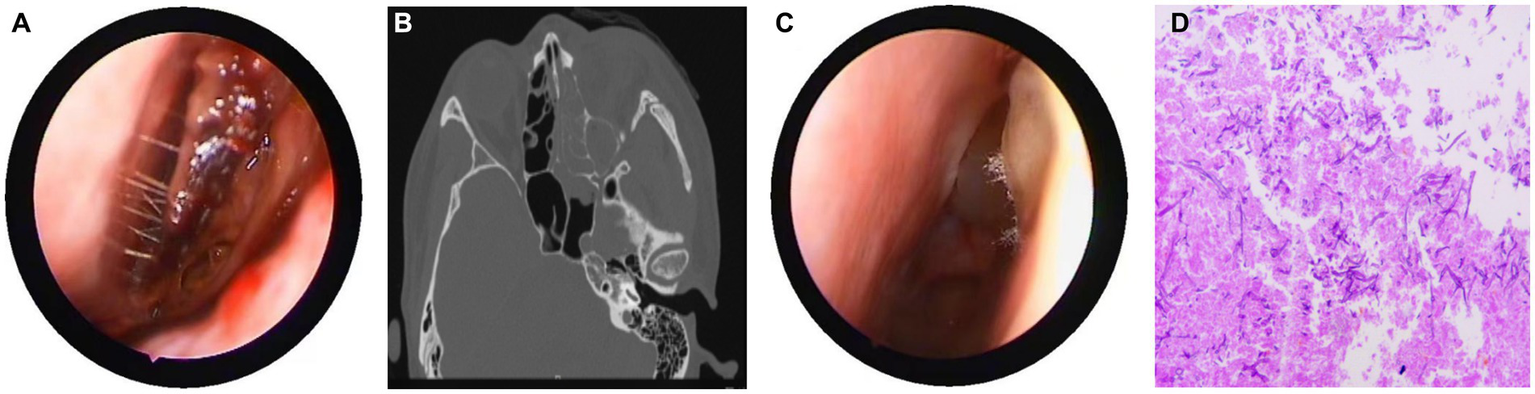

Figure 2

Nasal endoscopy, sinus CT, and pathological results. (A) Endoscopic examination showing pus in the left middle meatus and blood scab on the surface of the middle turbinate. (B) CT showed left ethmoid and frontal sinusitis, with thickening and swelling of the left medial rectus and inferior rectus muscles, and swelling of the soft tissues around the left orbit and cheek. (C) During the intraoperative nasal endoscopy, white hyphae were found in the left nasal cavity. (D) Postoperative pathology: a large number of fungal hyphae and spores were seen in the nasal and sinus mucosa.

On March 29, 2022, a 32-year-old male patient with systemic lupus erythematosus was admitted to the hospital due to recurrent cough for 1.5 months and abnormal kidney function for 1 month. The patient’s CT on February 22 suggested pulmonary infection, and multidisciplinary consultation in the outside hospital considered pulmonary aspergillosis (Figures 1A,B). After 23 days of treatment with caspofungin (50 mg qd), the patient’s lung condition improved (Figures 1C,D). Admission diagnosis: Systemic lupus erythematosus, lupus nephritis type IV + V, pulmonary aspergillosis. The patient received methylprednisolone and cyclosporine to control the primary disease, and voriconazole was taken orally to treat pulmonary aspergillosis after admission. On April 7th, the patient developed numbness in the left cheek, nasal congestion, runny nose, and fever. Endoscopic examination showed pus in the left middle meatus and blood scab on the surface of the middle turbinate (Figure 2A); CT showed left ethmoid and frontal sinusitis (Figure 2B). Two cultures of nasal secretion yielded no bacterial or fungal growth. The patient received additional piperacillin tazobactam (4.5 g q8h) anti-infection and nasal irrigation. During this period, the patient’s platelets decreased progressively, with a platelet count of 30×10^9/L on April 16th. Considering the low platelet count of the patient, invasive treatment was not recommended. The patient’s antibiotic was changed to meropenem (0.5 g q8h) combined with contezolid (0.8 g q12h), and gamma globulin (20 g qd) was administered for 3 days to enhance immunity. On April 17th, the patient’s left conjunctival swelling and soft tissue protrusion worsened compared to before. On April 19th, the patient experienced sudden vision loss in the left eye at night. The patient underwent emergency functional endoscopic sinus surgery to clear the lesions in the maxillary sinus, ethmoid sinus, frontal sinus, and orbit (Figure 2C). Intraoperative pathology reported: a large number of fungal hyphae and spores were seen in the nasal and sinus mucosa (Figure 2D). mNGS of the infected tissue in the sinus during the operation: Rhizopus (Figure 3). Following the surgery, the antibiotic regimen was modified to include meropenem (0.5 g q8h), contezolid (0.8 g q12h), amphotericin B 6 mg daily with a daily increase of 5 mg, and posaconazole suspension (200 mg q6h). The patient’s vision in the left eye showed some recovery 1 day after the surgery. Nevertheless, the patient suffered from severe agranulocytosis and extreme immunosuppression, resulting in an extremely weakened mental state and gradually declining consciousness. CT on April 25th showed brain parenchymal swelling, brainstem swelling and fuzzy, multiple low-density foci in the brain, and mild right shift of the midline, indicating intracranial infection with brain herniation formation. Eventually, the patient died due to systemic infection and multiple organ failure. The entire treatment process is summarized in Figure 4.

Rhizopus invading blood vessels can form blood clots, causing ischemia and necrosis of surrounding tissues. Antifungal drugs are difficult to reach the infected site, so surgical debridement is crucial. Nasal mucormycosis has typical endoscopic manifestations, such as dark purple crusts or pale mucosa (Figure 2A). Vaughan et al. found that the survival rate of surgical treatment within 12 days of onset of RCM is 61, 33% after 12 days, and only 21% for those without surgical treatment (15).